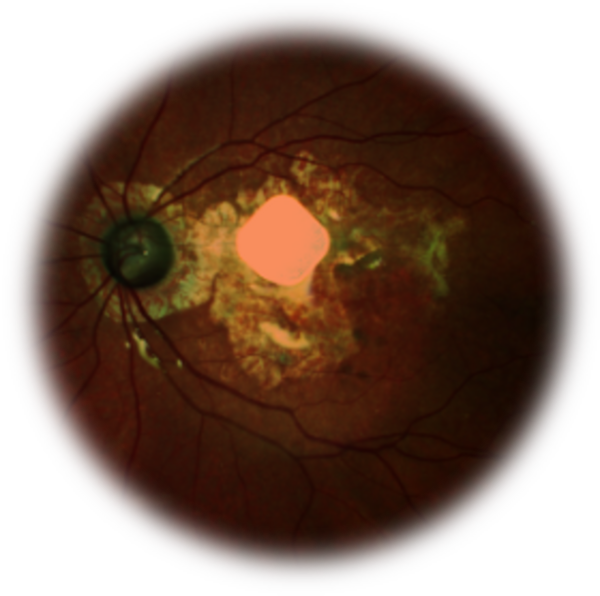

La dégénérescence maculaire atrophique liée à l'âge (DMLA) représente une progression délétère de la maculopathie liée à l'âge, caractérisée par des lésions rétiniennes avancées associées à des drusen et des pseudodrusen, ainsi qu'à des altérations des couches externes de la rétine et de l'épithélium pigmentaire rétinien (EPR). Elle se caractérise par un amincissement du tissu rétinien lié à la disparition des couches externes de la rétine et de l'EPR.

Notre objectif est de proposer aux ophtalmologistes des recommandations pour le diagnostic et la prise en charge de la DMLA atrophique. Le diagnostic repose sur l'imagerie multimodale .Dans certain cas, le diagnostic différentiel peut nécessiter des examens complémentaires, tels qu'une angiographie à la fluorescéine et/ou au vert d’indocyanine.

Les solutions thérapeutiques pour cette pathologie sont multidisciplinaires ; elles associent un suivi clinique régulier, un traitement médical, un soutien psychologique, une rééducation orthoptique et des aides visuelles optiques.